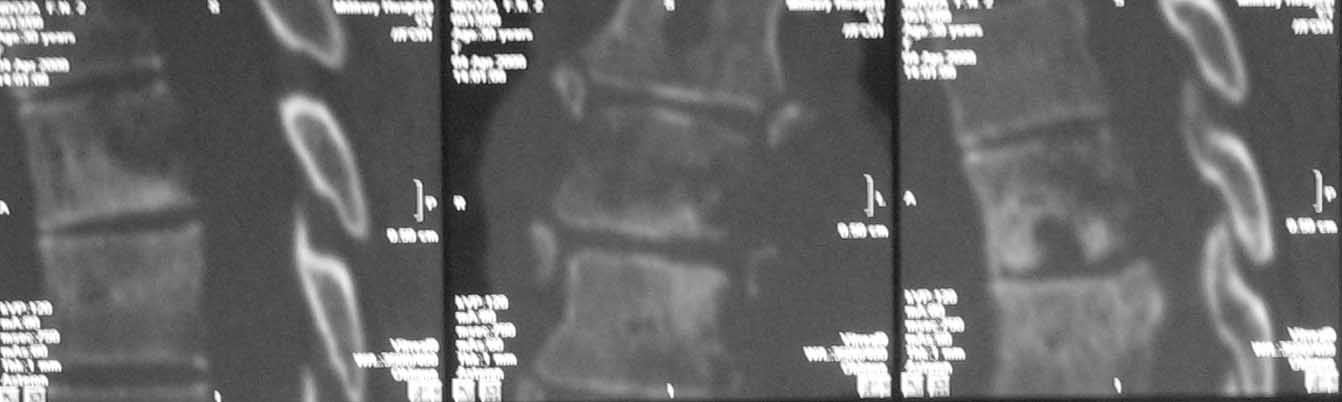

В решении вопроса о протяженности резекции тел позвонков, считаю нецелесообразным ориентироваться на данные МРТ, в том числе на МР реконструкции, так как значительное повышение Т2 сигнала, которое мы видим на представленных снимках, появляется уже на первой неделе заболевания вследствие цитотоксического отёка и только потом некроза (С.А. Тиходеев, А.А. Вишневский «Неспецифический остеомиелит позвоночника» 2004). На представленных КТ тело позвонка (м.б. ThVI?) повреждено полностью и задние его отделы включительно, по всей видимости, этот уровень соответствует максимальной компрессии спинного мозга.

Случай действительно не стандартный и по результататам операционной ревизии обойтись без первичной иснрументации не удалось. первым этапом выполнена задняя ТПФ, вторым - левосторонняя торакотомия (соответственно максимальным изменениям паравертебральных тканей). при ревизии выявлено, что "жидкого" гноя нет, позвонки окружены гнойными вялыми, практически не кровоточащими грануляциями, тела позвонков Т5-9, включая 8 представляют собой "медовые соты ", фрагменты тел позвонков легко удаляются даже пинцетом. спинной мозг также сдавлен гнойными грануляциями. Тела Т5-9 удалены полностью. Установлен пористый никелид титана, обильно "сдобренный" цефобидом. Проточно-промывное дренирование.